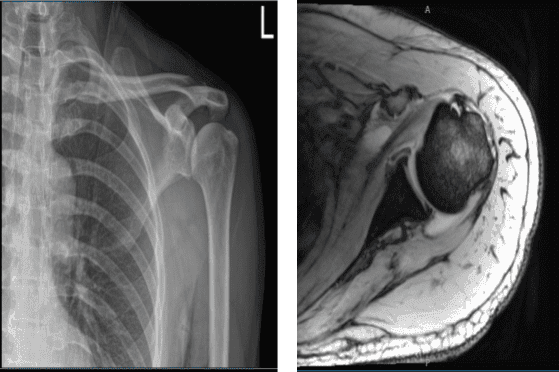

The patient was seen by me in the office with complaints of shoulder pain following an accident. His X-ray showed No abnormal soft tissue calcification is present.

Acromioclavicular joint reveals no significant abnormalities. The patient was treated conservatively, but failed. An MRI was done, which showed a rotator cuff tear of the left shoulder.

MRI of the left shoulder